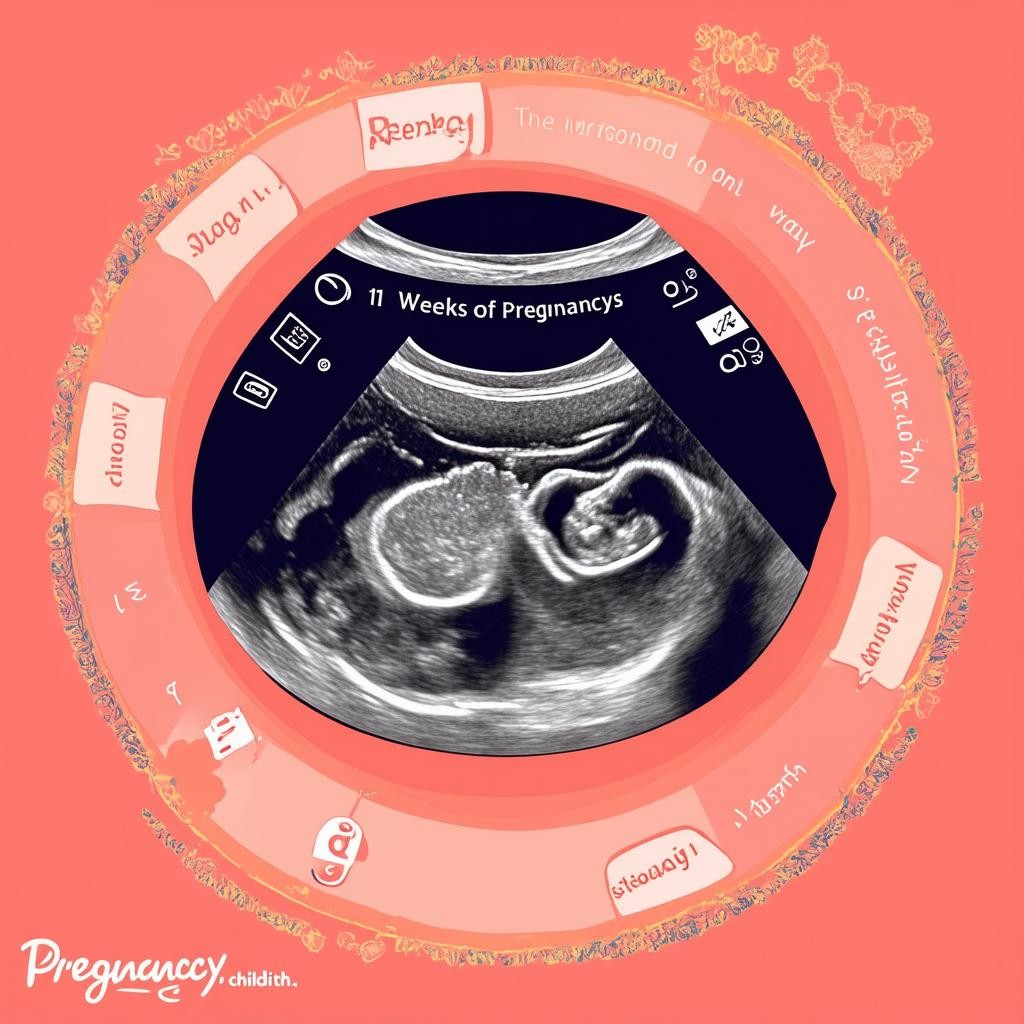

УЗИ на 11 неделе беременности

Ультразвуковое исследование на этом сроке позволяет оценить развитие плода и выявить возможные патологии. Врач проверяет:

- Размер плода (копчико-теменной размер — КТР).

- Частоту сердечных сокращений.

- Толщину воротникового пространства (ТВП) для исключения хромосомных аномалий.

- Расположение плаценты и количество околоплодных вод.

УЗИ на 11 неделе — важный этап пренатальной диагностики, который помогает убедиться в нормальном течении беременности.